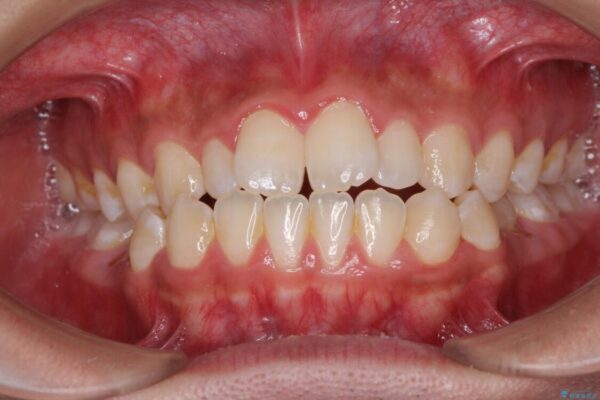

治療後について

下顎の残存乳歯は小臼歯よりも大きいため、スペースを閉じるために長い期間を必要としますが、予想通りに長期間を要することとなりました。

受け口傾向の方の抜歯矯正は、下顎前歯が舌側に倒れることで歯肉退縮を起こしやすいことが知られていますが、ワイヤーに工夫をすることでリスクを軽減させています。

治療後

• 口元の突出感を改善 受け口傾向の咬み合わせの抜歯矯正 治療後画像